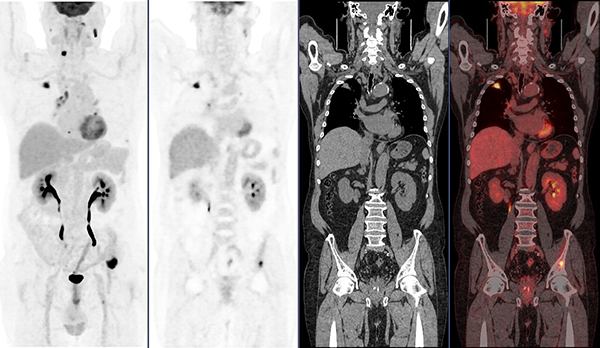

日前,66岁的文老伯因右侧头部有肿物10多天到我院就诊,头颅CT、MR检查及手术病理提示转移性皮质腺癌。那么,原发灶是什么,有没有其他远处转移,怎样的治疗方案更好?文老伯和家人非常茫然。

就在这时,医生介绍了一个评价分期的利器:PET/CT。通过PET/CT全身扫描成像,结果显示文老伯右肺上叶周围型肺癌,双侧颈部、纵隔及肺门多发淋巴结转移,第6颈椎椎体、第8胸椎右侧横突、左侧第8后肋、左侧髂骨多发骨转移。了解全身情况后,医生运用PET/CT的检查结果指导穿刺活检,精准选择最佳活检部位,提高活检准确率,穿刺结果显示肠型腺癌,低分化区30%,高分化区70%,为临床医生提供了全面精细的疾病诊治依据。